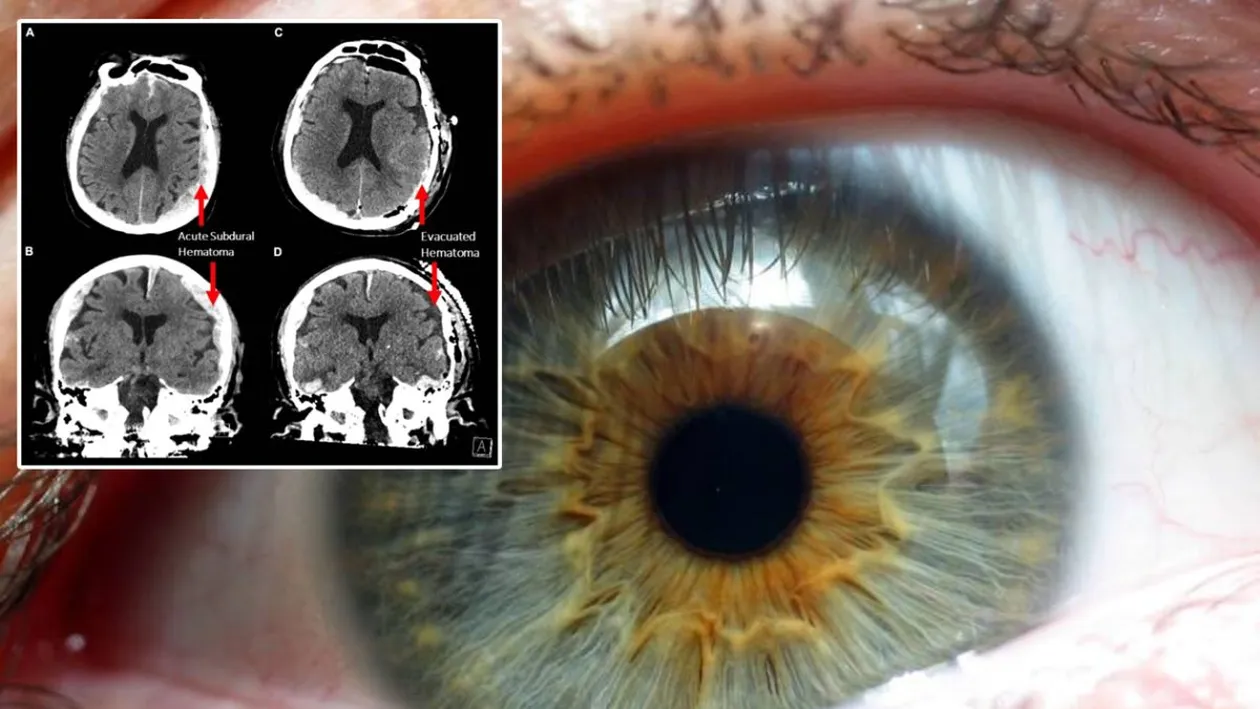

Descoperirea savanților. Sursă foto: Frontiers in Aging Neuroscience

În timpul morții unui pacient de 87 de ani, medicii au înregistrat o activitate neobișnuită. Descoperirea a venit în timp ce înregistrau un creier care era în ultimele sale momente de activitate. Ceea ce au observat confirmă un fapt știut despre moarte de mii de ani, dar care părea ireal.

Oamenii de știință au efectuat un studiu pe creierul unei persoane care se afla în ultimele sale clipe de viață. Pacientul de 87 de ani dintr-un spital din Columbia le-a deschis ochii medicilor cu privire la un detaliu care este greu de acceptat.

Conform înregistrării activității creierului muribundului, creierul pacientului a produs oscilații neuronale care apar când îți aduci aminte de ceva sau când visezi. Durata acestora este de câte 30 de secunde, timp în care momentele din viață reapar. Astfel, descoperirea cercetătorilor confirmă un mit atât de vechi și cunoscut, acela că îți trece viața prin fața ochilor atunci când mori. (CITEȘTE ȘI: Se dau bani de la Guvern! Ce trebuie să faci ca să primești 50 de lei pe zi)